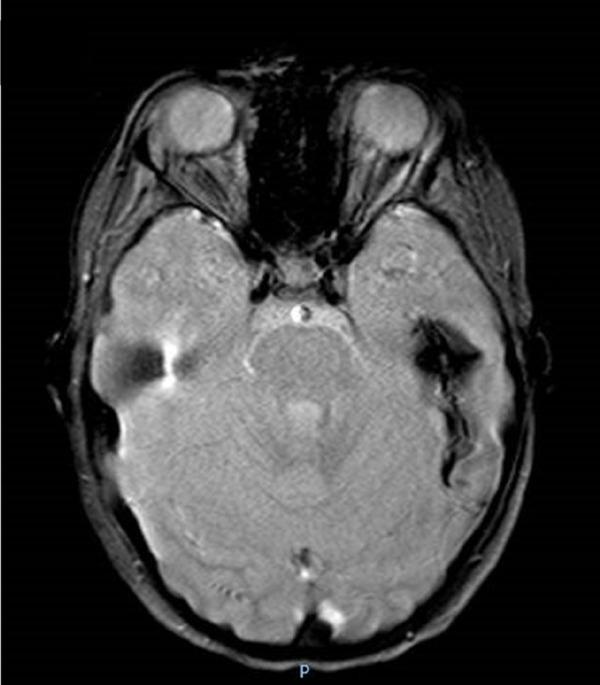

Systemic autoinflammatory diseases (SAIDs) are disorders of innate immunity, which are characterized by unprovoked recurrent flares of systemic inflammation often characterized by fever associated with clinical manifestations mainly involving the musculoskeletal, mucocutaneous, gastrointestinal, and nervous systems. Several conditions also present with varied, sometimes prominent, involvement of the vascular system, with features of vasculitis characterized by variable target vessel involvement and organ damage. Here, we report a systematic review of vasculitis and vasculopathy associated with inborn errors of immunity.

系统性自身炎症性疾病(SAIDs)是先天性免疫紊乱疾病,其特征为无明显诱因的全身性炎症反复发作,常伴有发热,并伴有主要累及肌肉骨骼、皮肤黏膜、胃肠道和神经系统的临床表现。一些疾病还伴有血管系统的不同程度受累,有时受累较为显著,具有血管炎的特征,表现为不同的靶血管受累和器官损害。在此,我们报告一项关于与先天性免疫缺陷相关的血管炎和血管病变的系统综述。